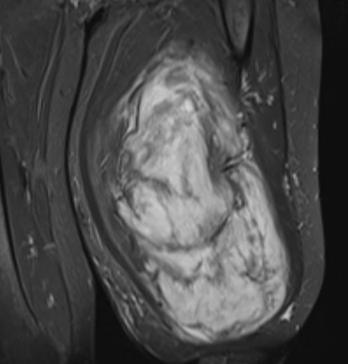

Mardin’de yaşayan H.T. (42), 3 yıl önce sağ baldırının arka kısmında oluşan ve başlangıçta yumurta büyüklüğünde olan kitlenin zamanla büyümesi üzerine Dicle Üniversitesi Tıp Fakültesi Hastanesi Ortopedi ve Travmatoloji Bölümü’ne başvurdu. Muayenede yumuşak doku kitlesi olduğu değerlendirilen şişliğin alınması için Ortopedi ve Travmatoloji Anabilim Dalı Öğretim Üyesi Prof. Dr. Emin Özkul ve ekibi tarafından ameliyat kararı verildi. Yaklaşık 2 saat süren operasyonla kitlenin çıkarıldığı, kitlenin 5 kilo 668 gram geldiği belirtildi.

Prof. Dr. Emin Özkul, vücutta görülen kitlelere büyümeden müdahale edilmesi gerektiğini ifade ederek, “Hastamız 42 yaşında bir kadın. Komşu şehir Mardin’den geldi. Bölge hastanesi olduğumuz için bu tür hastalar Mardin’den, Şırnak’tan ve diğer illerden çok geliyor. Bu hastalara önerimiz; ‘küçük bir kitle, ağrısız bir kitlem var, ele gelen bir şişliğim var ama bunda ağrı olmadığı için herhangi bir şey olmaz’ dememeli. En yakın sağlık kuruluşuna başvurup en azından kitlenin bir öneminin olup olmadığını teyit edilmesi, bir uzman tarafından bunun doğrulanmasını istiyoruz. Bu hasta da 3 yıl önce fark edilmiş küçük bir kitle, zamanla çok büyük boyutlara, yaklaşık 6 kiloya varan boyutlara varmıştı. Neredeyse bütün bacak boyu yayılan bir kitlesi mevcuttu. Bu kadar büyümenin şöyle sıkıntıları oluyor, kişinin bacağında, kolunda fonksiyon kaybına, yeri geliyor ekstremite kaybına, yani bacağını kaybetmesine yol açabilecek sıkıntılara yol açıyor. Küçükken bunlarla baş etmek daha kolay. Kişinin ekstremitesinde, bacağında, kolunda bir sıkıntı yaratmadan bunları telafi etmek, bunları alıp çıkartmak, ameliyatla bunları tedavi etmek daha kolayken bu boyutlara vardığında kişinin bacağında, kolunda fonksiyon kaybı, sakatlık riski çok yüksek oluyor. Bu sebeple küçükken önleminin alınmasında yarar var” dedi.

Kitlelerin görülmesi halinde sağlık kuruluşlarına başvurulması gerektiğini belirten Prof. Dr. Özkul, “Hastamızda yaklaşık olarak 3 yıl önce şikayetleri başlamış. Sonra zaman içerisinde hızla büyüyen bir kitleye sahipti. Şanslıydı ki herhangi bir sinirine zarar vermemişti. Hayatına fonksiyon bozukluğu olmadan devam edebilecek. Bölgemize yaşayan ve ülkemizde yaşayan herkese şunu söylüyoruz. Küçük de olsa yumuşak doku kitlelerini önemsemeleri ve uzman görüşü almalarını öneriyorum. Bu hastadan 5 kilo 668 gramlık bir kitle çıkarttık. Bu benim mesleki yaşamım boyunca çıkarttığım en büyük kitlelerden bir tanesiydi. Biraz daha büyük boyutlara varmış olsa kişinin bacağını kurtarma şansınız olmuyor. Bu sebeple bunlara dikkat etmek gerekiyor. Hızlı büyüyen bir kitleniz var ise, ağrısız da olsa mutlaka ve mutlaka tedavi için en yakın sağlık kuruluşuna veya bizim üniversitemizin polikliniklerine başvurabilirsiniz” diye konuştu.